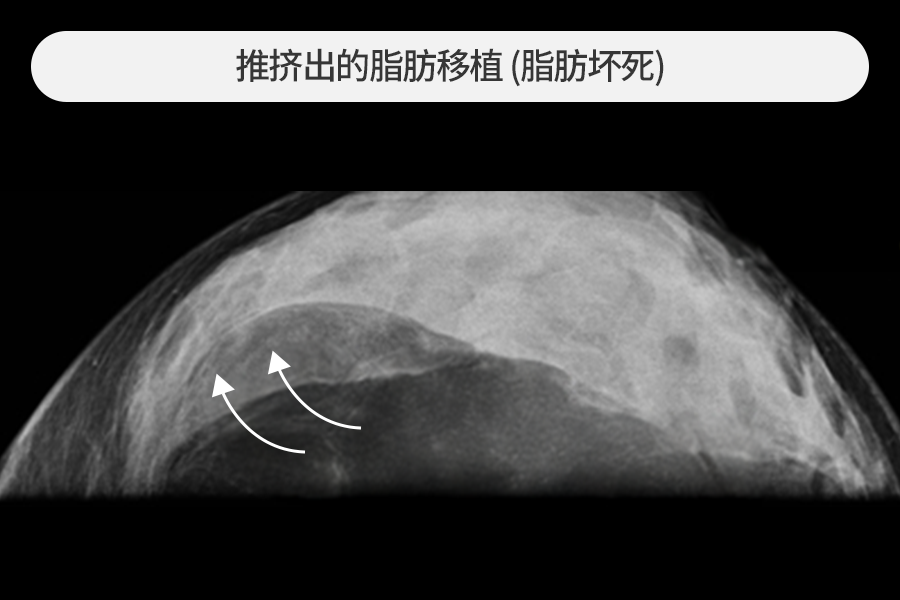

4~5cm 大小的脂肪移植硬块去除

该患者因胸部脂肪移植后摸到乳房硬块而来院,观察到4~5cm大小的巨大钙化硬块。

尺寸较大的脂肪移植硬块发生急性炎症时风险较高,需要尽快去除。

在超声引导下保留正常组织,仅安全去除了硬块。

融化的脂肪横跨乳房形成带状的情况

未存活的脂肪坏死团块横跨乳房形成长带,内窥镜检查中也观察到大量钙化。

在超声和内窥镜等影像设备引导下,去除了各种脂肪移植副作用病变。